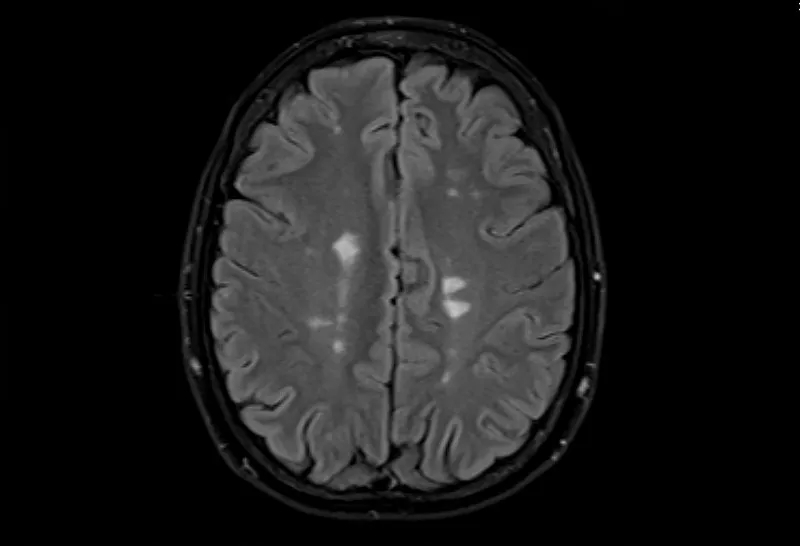

多發性腦硬化癥的磁共振成像,軸位Flair視圖

• 大腦的MRI掃描可以顯示損傷區域,但沒有單一的測試可以診斷MS。

測試的組合用于診斷MS。最好的測試是對您的大腦和脊髓進行核磁共振檢查,以檢測損傷區域。您可能還需要進行血液檢查、腰椎穿刺和測量神經活動的測試。